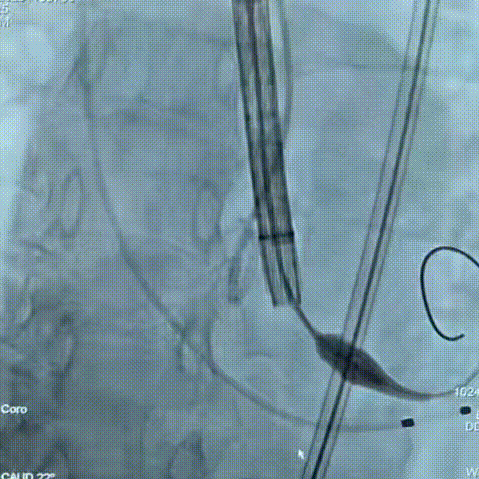

手术过程

手术过程:在右股动脉穿刺建立通路后,顺利送入大鞘,经食道超声及血管造影确认路径稳定。18mm球囊预扩后评估冠脉灌注良好,后将Prostyle A® AV26瓣膜精准释放于目标位置,超声显示无瓣周漏,术后即刻造影显示无明显反流,术前PGmean40mmHg,术后导管测平均跨瓣压差8mmHg,心功能明显改善,患者生命体征平稳。

定位

迅速锚定

最终造影形态位置良好,无瓣周漏